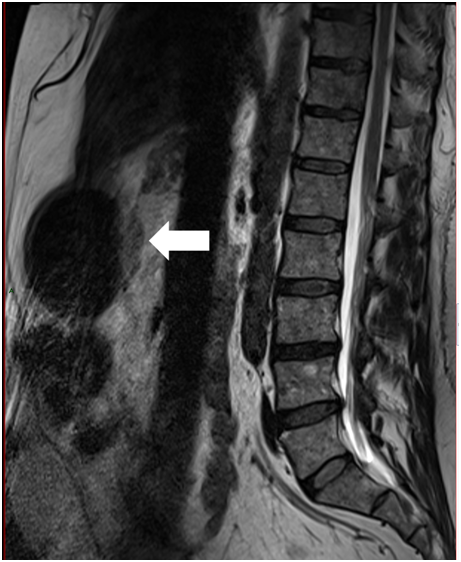

Figure 2 Magnetic resonance with intramedullary lesion in the sternum.

The patient consulted with a cardiology team where an electrocardiogram and an exercise test were performed, being reported normal. He was then referred to the orthopedics service due to shoulder pain persistence. A shoulder x-ray showed a tumor in the left thorax measuring 78.99mm in diameter (Figure 1). In follow up studies, a left humeral lesion of neoplastic appearance was revealed. In the magnetic resonance an intramedullary lesion is reported in the sternum, incidentally, a solid mass is observed in the left lung, it also shows tendinitis of the rotator cuff and subacromial impingement (Figures 2-4). Therefore, it is decided to perform a Computed Tomography scan which reported atelectasis mainly in the left upper lobe and a tumor measuring 65mm (Figure 5). The Positron Emission Tomography - Computed Tomography scan result was an increase of the metabolism by neoplastic activity, lymphadenopathy and bone lesions, hepatosplenomegaly and non- specific alterations in the colon (Figure 6).